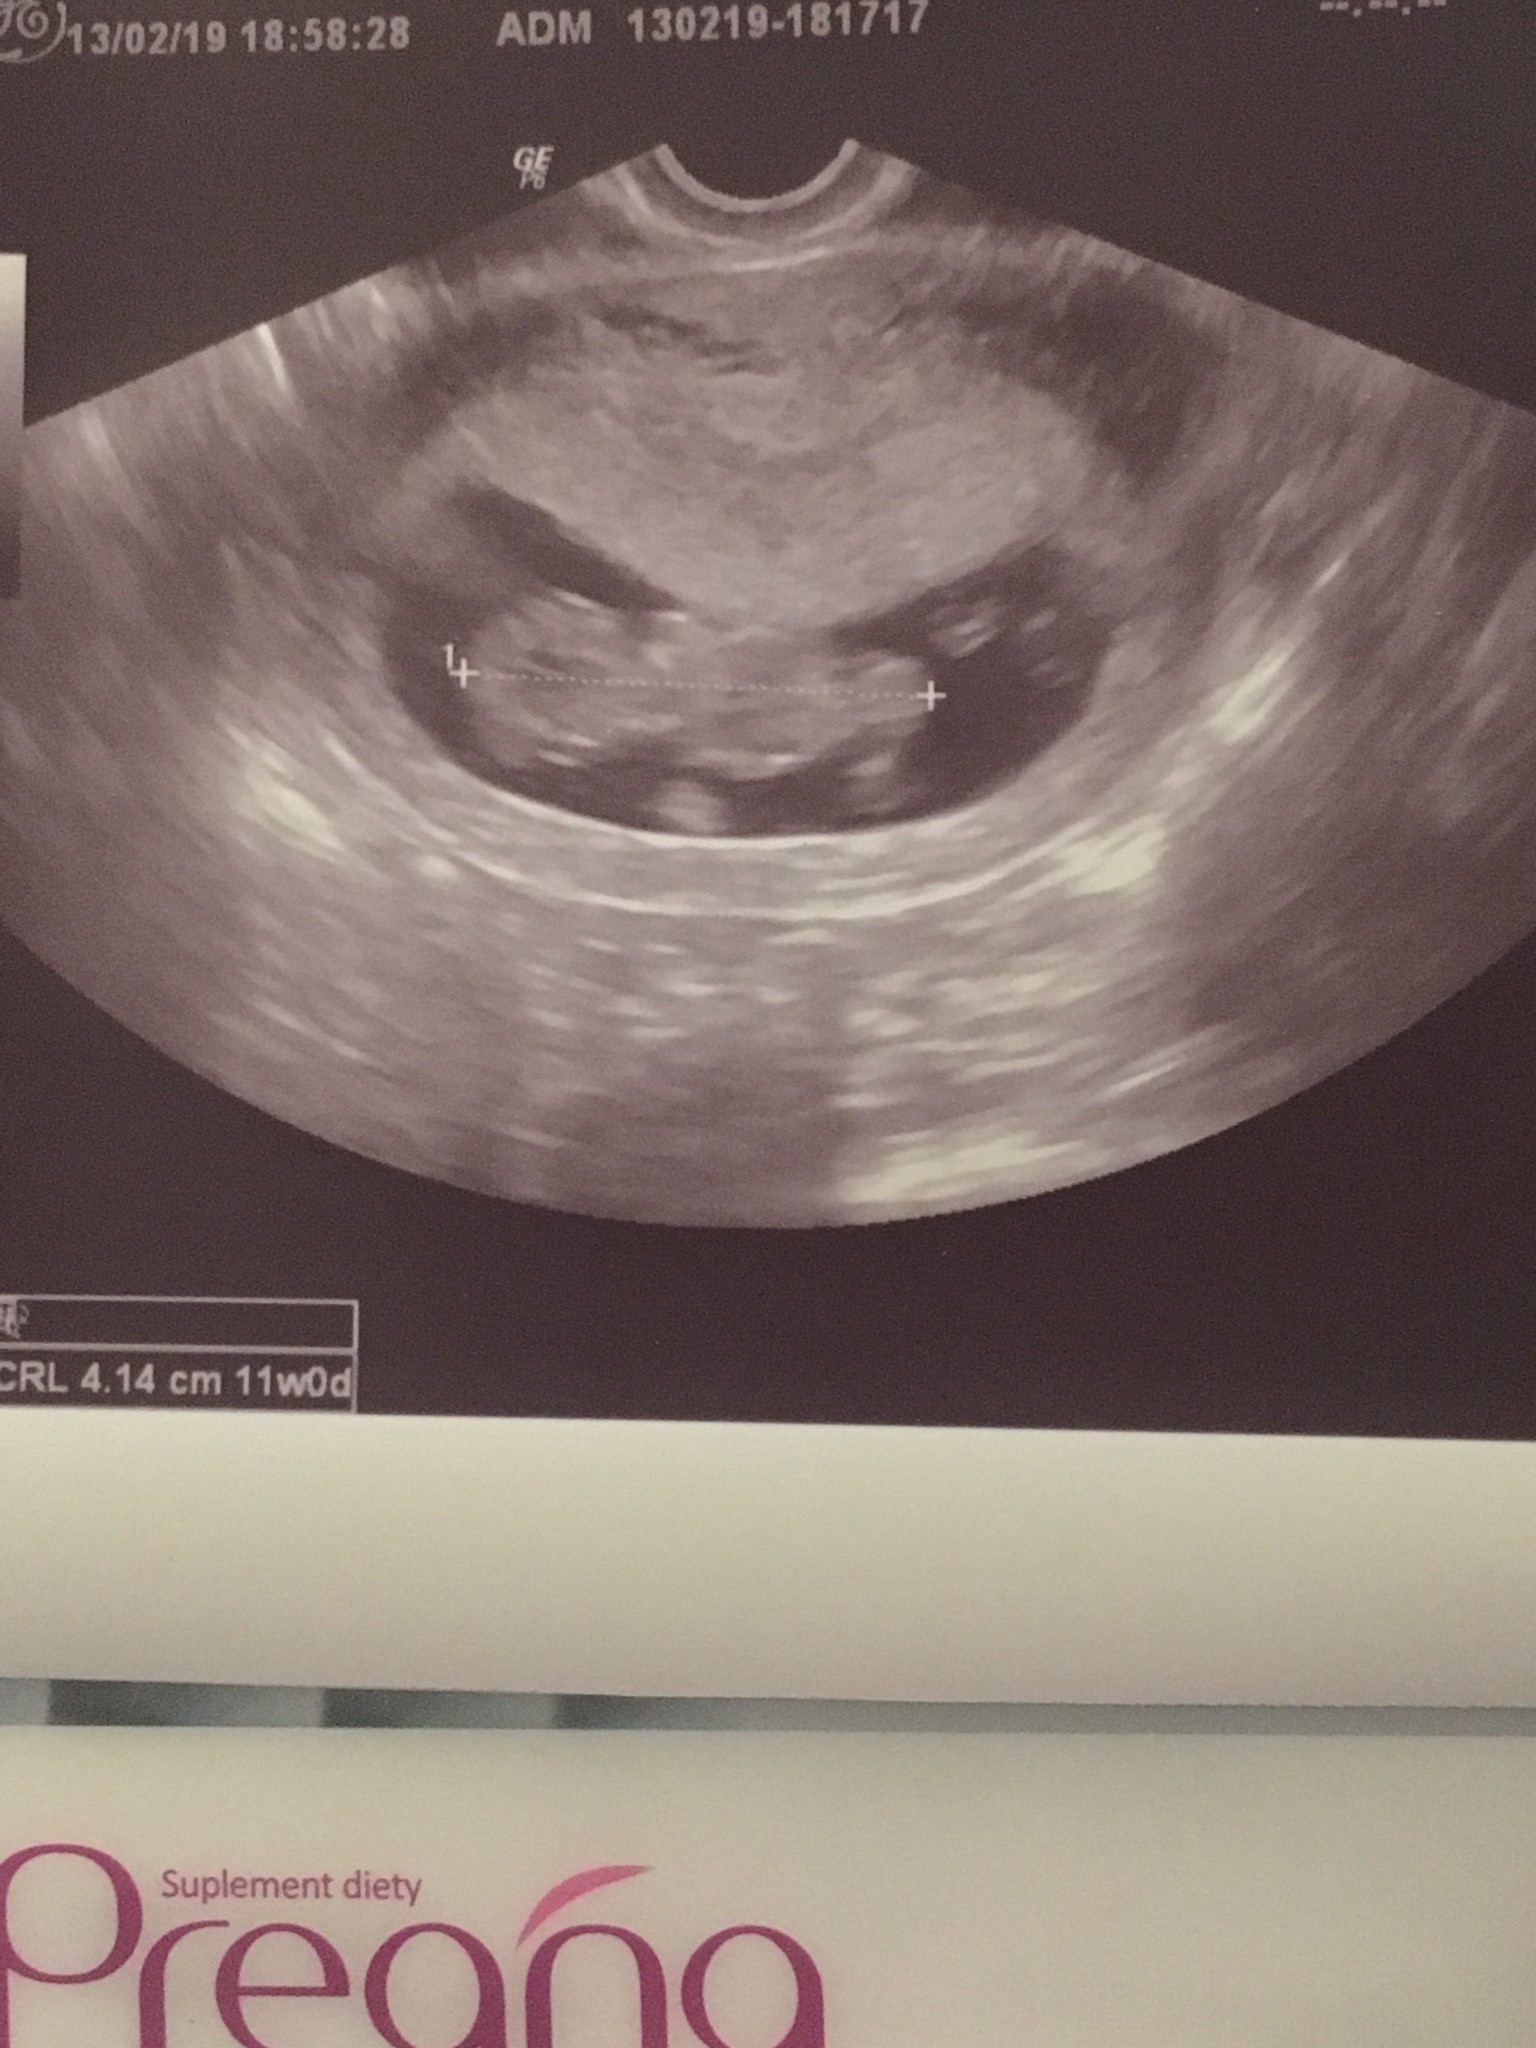

Mój bobasek [emoji173]️[emoji173]️

Wszystko ok, serduszko pięknie bije, karta ciąży załączona, maluszek ma już 4cm :)

I 28.02 jestem umówiona na prenatalne :)